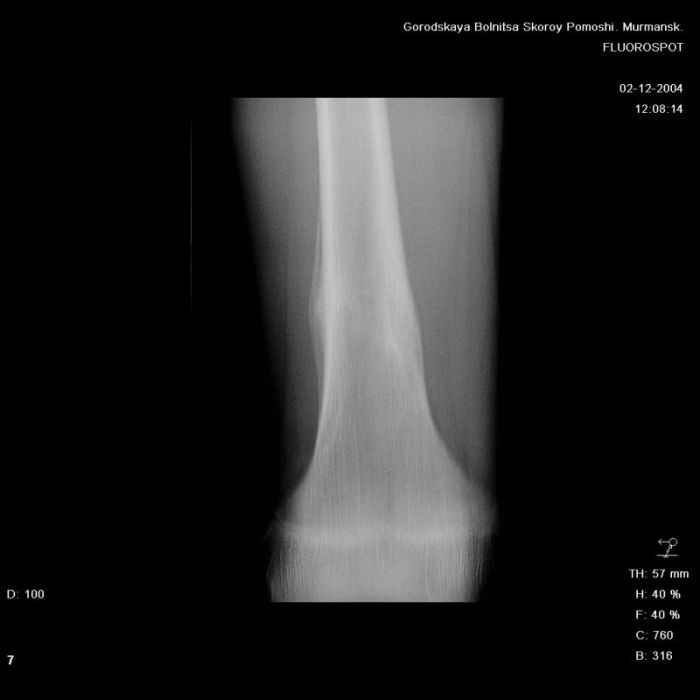

Здравствуйте, уважаемые коллеги!Представляю вашему вниманию интересный случай и пока что непонятный для меня в диагностическом плане. На днях в наше отделение (детской ортопедии и травматологии) поступил 13-летний мальчик по направлению из поликлиники с диагнозом: остеома нижней трети правого бедра.

Анамнез практически никакой: в следствие травмы (растяжение связок коленного сустава) от 07.11.2004 выполнены Rg-граммы в травмпункте и обнаружено опухолевидное образование. Первичные Rg-граммы я не публикую, так как они заметно худшего качества, да и динамики за прошедшие три недели не отражают. Болевой синдром купирован в течение трёх дней. В настоящий момент мальчика ничего не беспокоит. Ходьба не нарушена, опухоль пальпируется с трудом по задней поверхности в н\3 правого бедра, пальпация безболезненна, объем движений в суставах правой нижней конечности полный и симметричный. Кожа над опухолью не изменена.В нашей клинике проведено дополнительное обследование: общие анализы крови и мочи, биохимия крови без особенностей. Выполнены Rg-граммы на цифровом Siemens обычные и продольные томограммы срезами 3-5 мм, а также компьютерная томография поперечными срезами по 5 мм. Прошу обратить внимание, что на приведённых томограммах видны две полости 10х15 мм и 15х60 мм. Также имеются два опухолевидных образований наслаивающихся друг на друга: уплощённое и вытянутое 10х100 мм и элипсовидной формы 15х30 мм. Это хорошо заметно на фото a_1.jpg c_1.jpg и d_1.jpg. Плотность внутри полостей 125% от плотности костномозгового канала, плотность наружного опухолевидного образования 55% от плотности кортикального слоя. Также отмечается линия перелома по центру наружного опухолевидного образования.Исходя из полученных данных мнения в плане диагноза несколько разделились от 1)сочетания кортикальной фиброзной дисплазии и латентно протекавшего маршевого перелома н\3 правого бедра до 2)остеосаркомы. В отношении первого варианта не сходится отсутствие клиники при переломе такой крупной кости как бедро, второй вариант вообще оставлю без комментария, ибо некомпетентен. Хотелось бы услышать мнения коллег, с удовольствием ознакомлюсь с любыми предположениями и замечаниями.С уважением, Александр Е. КлоковОтделение детской ортопедии и травматологииБСМП г. Мурманска.